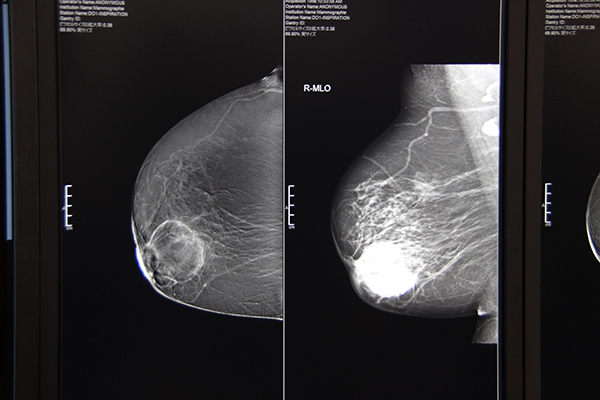

4月12日に発売したばかりの最上位機種となるデジタルマンモグラフィシステム「MAMMOMAT Revelation」は,より高度に精密検査を行えるよう多機能化された。新たに造影マンモグラフィが可能になり,MRI検査非適応の患者に対して造影検査を提供する。また,撮影と同時に乳腺密度を計測し,客観的な評価を支援する。バイオプシー検査も進化し,トモシンセシス画像(振り角左右50°)を用いることで,より精度の高いターゲッティングを簡単に行えるようになった。圧迫板は素材や形状を工夫することで,患者の快適性の向上も追究している。

デジタルマンモグラフィシステム「MAMMOMAT Revelation」

MAMMOMAT Revelationによる造影マンモグラフィ画像